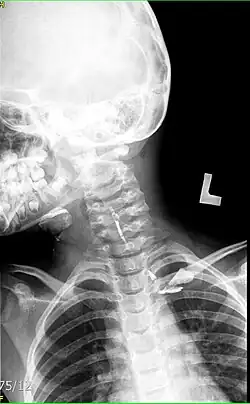

W badaniu histopatologicznym, torbiel skrzelopochodna wysłana jest urzęsionym nabłonkiem i wypełniona bogatą w białko treścią śluzową. Przy współistniejącym wtórnym zakażeniu w świetle torbieli stwierdza się treść ropną. W tych przypadkach skóra szyi nad torbielą ulega obrzękowi i zaczerwienieniu. Czasami torbiel może przebić się na zewnątrz- na powierzchnię skóry szyi. Torbiele wyścielone są nabłonkiem wielowarstwowym płaskim rogowaciejącym (miejscowo niekiedy nabłonkiem walcowatym migawkowym), pod którym widoczny jest gęsty naciek z limfocytów z ośrodkami rozmnażania grudek chłonnych. Badania obrazowe pomocne w diagnostyce torbieli skrzelopochodnej to: USG szyi oraz TK, w której torbiel ma postać cienia okrągłego, wewnątrz znajduje się płyn o gęstości odpowiadającej wydzielinie śluzowej.